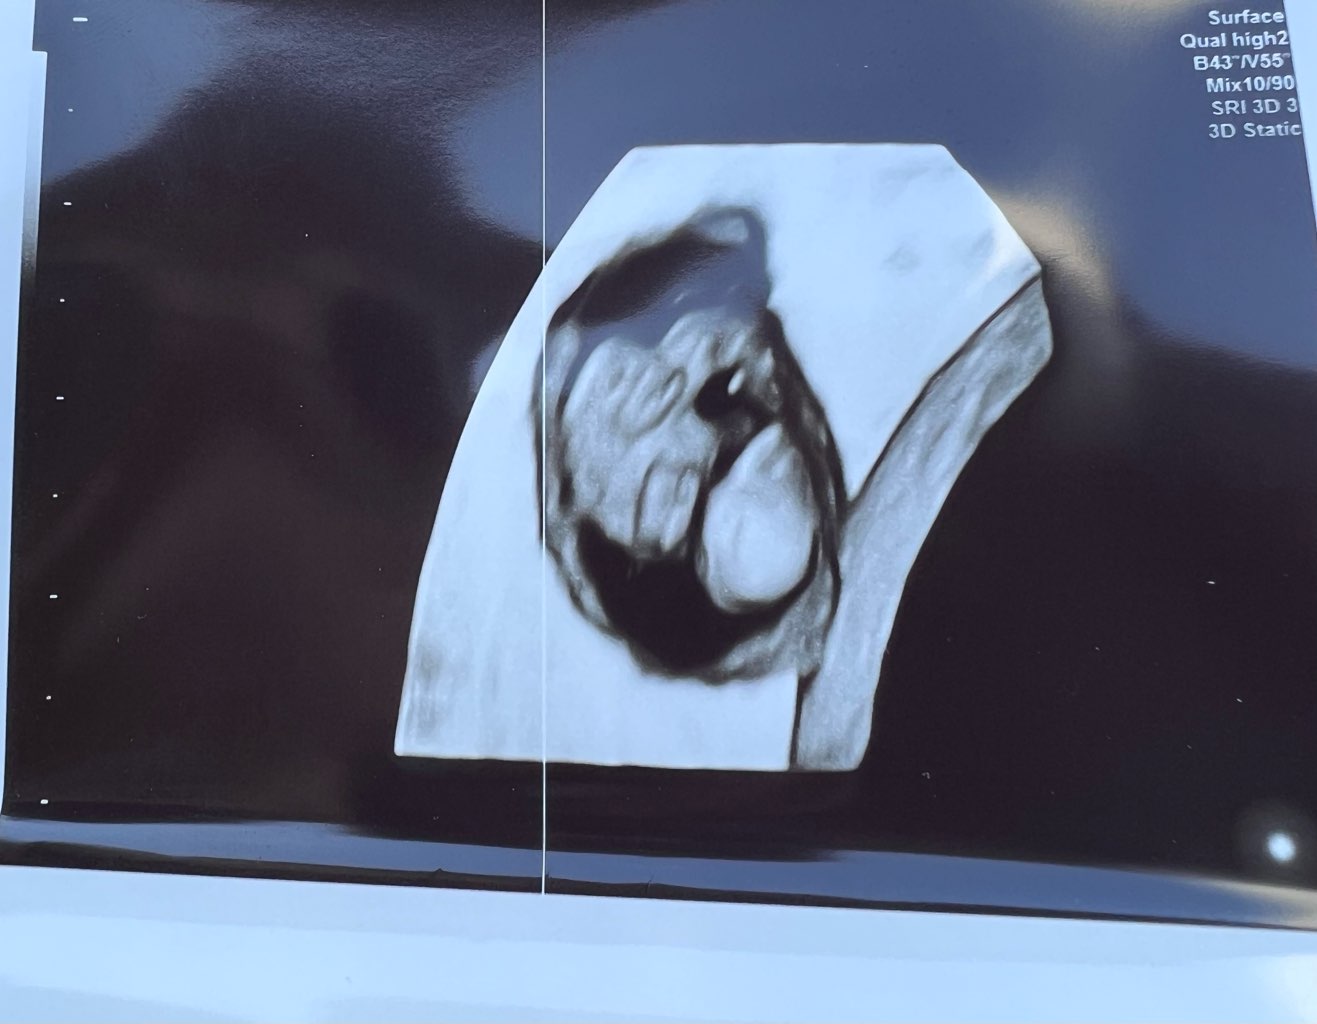

Mamy dorodnego dziecioka z bijącym serduszkiem. Lekarz nie puszczał bo mówił, że dość kontrowersyjna kwestia ostatnio i badania, więc lepiej dmuchać na zimne (choć sam kiedyś puszczał i nie było żadnego wpływu) i dopiero od 10tc lepiej. Wg OM 7+1, a wg USG 7+5 i termin się zmienił z 27.12 na 23.12, ale to jak wiadomo jest ruchome